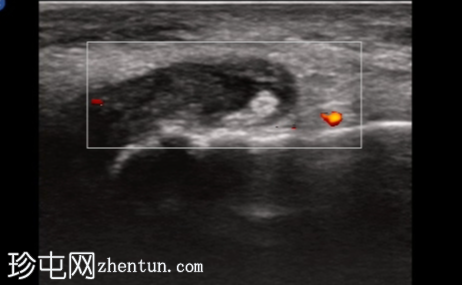

纵轴切面

第一跖趾关节纵轴切面

治疗后2周

关节积液伴轻度滑膜增生。高回声不规则沉积物,符合尿酸钠晶体沉积的典型表现。彩色多普勒成像显示滑膜充血活跃,符合急性炎症活动。